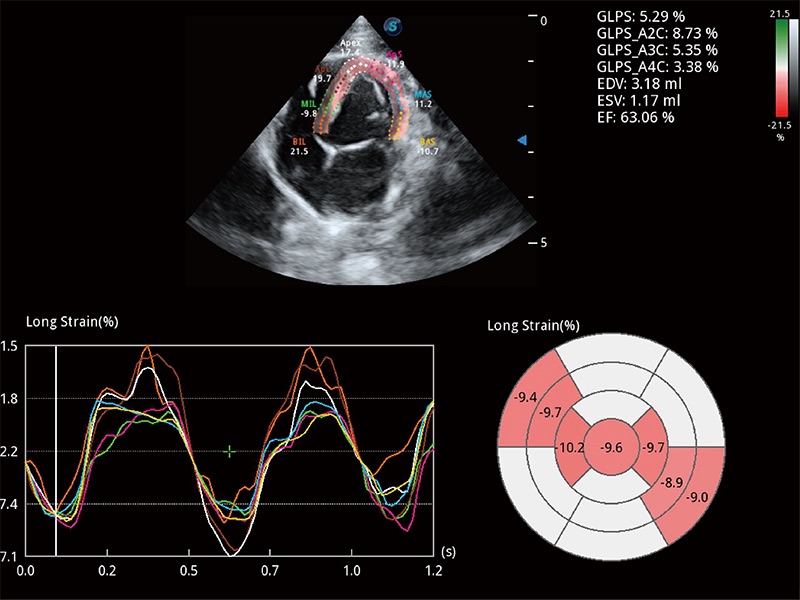

Die präzise Erkennung der linksventrikulären Wandbewegung mit globalem 2D-Speckle-Muster-Tracking ermöglicht eine genaue quantitative Analyse einschließlich Dehnung, Dehnungsrate, Auslenkung, Geschwindigkeit usw. der Myokardwände.